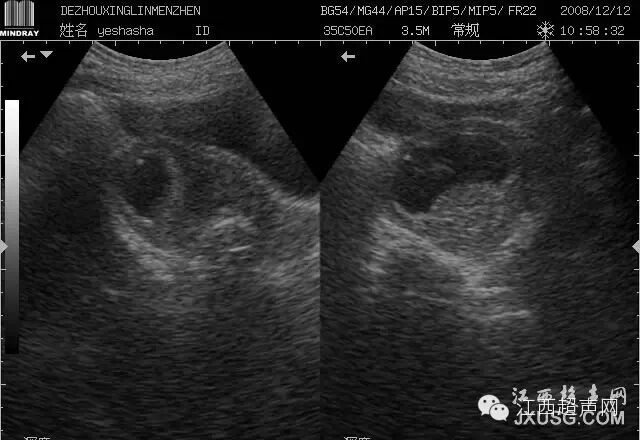

58.这是我一个大学同学,脾周围弧形低回声区,当时觉得很奇怪,也不知道是不是病变,后来她自己回去做了CT,没有问题,后来又看见过一次这样的病例,就没下诊断了!现在想想,是不是就是有的人说的左肝延伸过来覆盖了脾脏?当时也没注意这一点!

彩超伪像是什么60个超声诊断中容易误诊的正常结构_https://www.jmylbn.com_新闻资讯_第12张